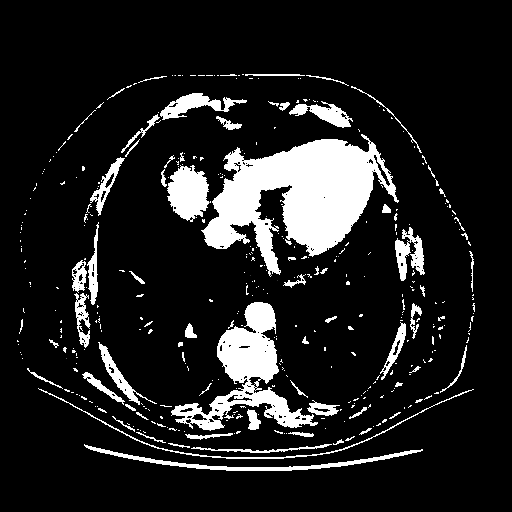

Reconstructed NATIVE CT scan (cycle consistency)

Full window (WL 1023.5, WW 4095 β†’ Low βˆ’1024, High +3071)

Actual HU range: [-1024.0, 3071.0]